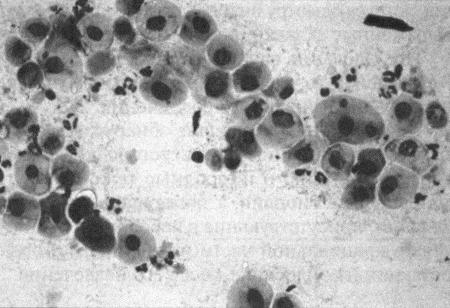

Фиг. 2.2.

Вагинальные выделения кошки (а). Выделения, типичные для фазы эструса. Большая часть клеток представляет собой безъядерные кератинизированные клетки или клетки с пикнотическим ядром. Присутствуют промежуточные клетки (b). Выделения, характерные для метэструса, — «течки», иногда наблюдаемой у кошек в конце эструса. Присутствуют поверхностные и промежуточные клетки, повышено содержание лейкоцитов. Этот короткий метэструс наблюдается в течение 24–48 часов (см. Приложение)